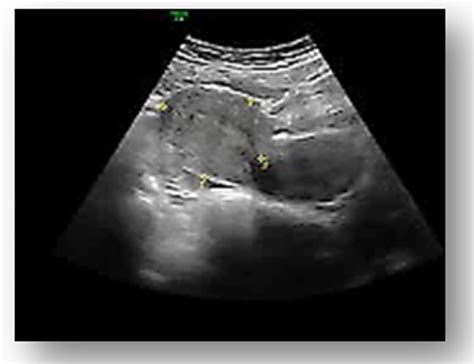

• Evaluate the placenta and amniotic fluid levels.

During your 13 week pregnancy sonography, you will lie on an examination table, and a gel will be applied to your abdomen. The sonographer will use a transducer to send sound waves through your uterus, creating images of your baby on a screen. The procedure is painless and non-invasive, taking about 20 to 30 minutes to complete.

After the 13 week pregnancy sonography, the sonographer will provide you with initial findings, but a detailed report will be sent to your healthcare provider. The results will include measurements and observations from the scan, which will be used to assess your baby's health and development.